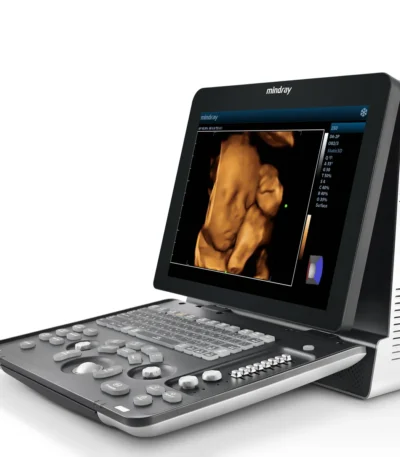

Mindray DC-N3 Pro Ultrasound Machine

The Mindray DC-N3 Pro is an enhanced version of the popular DC-N3 model, offering superior imaging performance, improved workflow, and advanced diagnostic tools in a compact and ergonomic design. It is a color Doppler ultrasound system suitable for a wide range of clinical applications — from general imaging to obstetrics, gynecology, cardiology, and small parts examinations.

Engineered with Mindray’s latest imaging innovations, the DC-N3 Pro delivers high-resolution images, fast processing, and user-friendly operation, making it ideal for hospitals, clinics, and diagnostic centers seeking a reliable and efficient ultrasound solution.